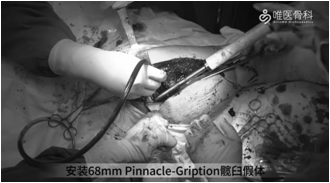

安装髋臼假体:给予脉冲冲洗后,依次进行68mm Pinnacle-Gription髋臼假体的安装、钻孔、拧入螺钉和安装聚乙烯衬垫。

注意:①臼杯前倾可适当妥协,以尽可能使臼杯与宿主骨充分接触,本病例假体与宿主骨接触面积为60%。②打入髋臼假体时,动作要轻柔,避免因暴力出现骨折。③螺钉固定时,尽量使用多个螺钉将髋臼杯固定到宿主骨上以提供整个结构的稳定性。